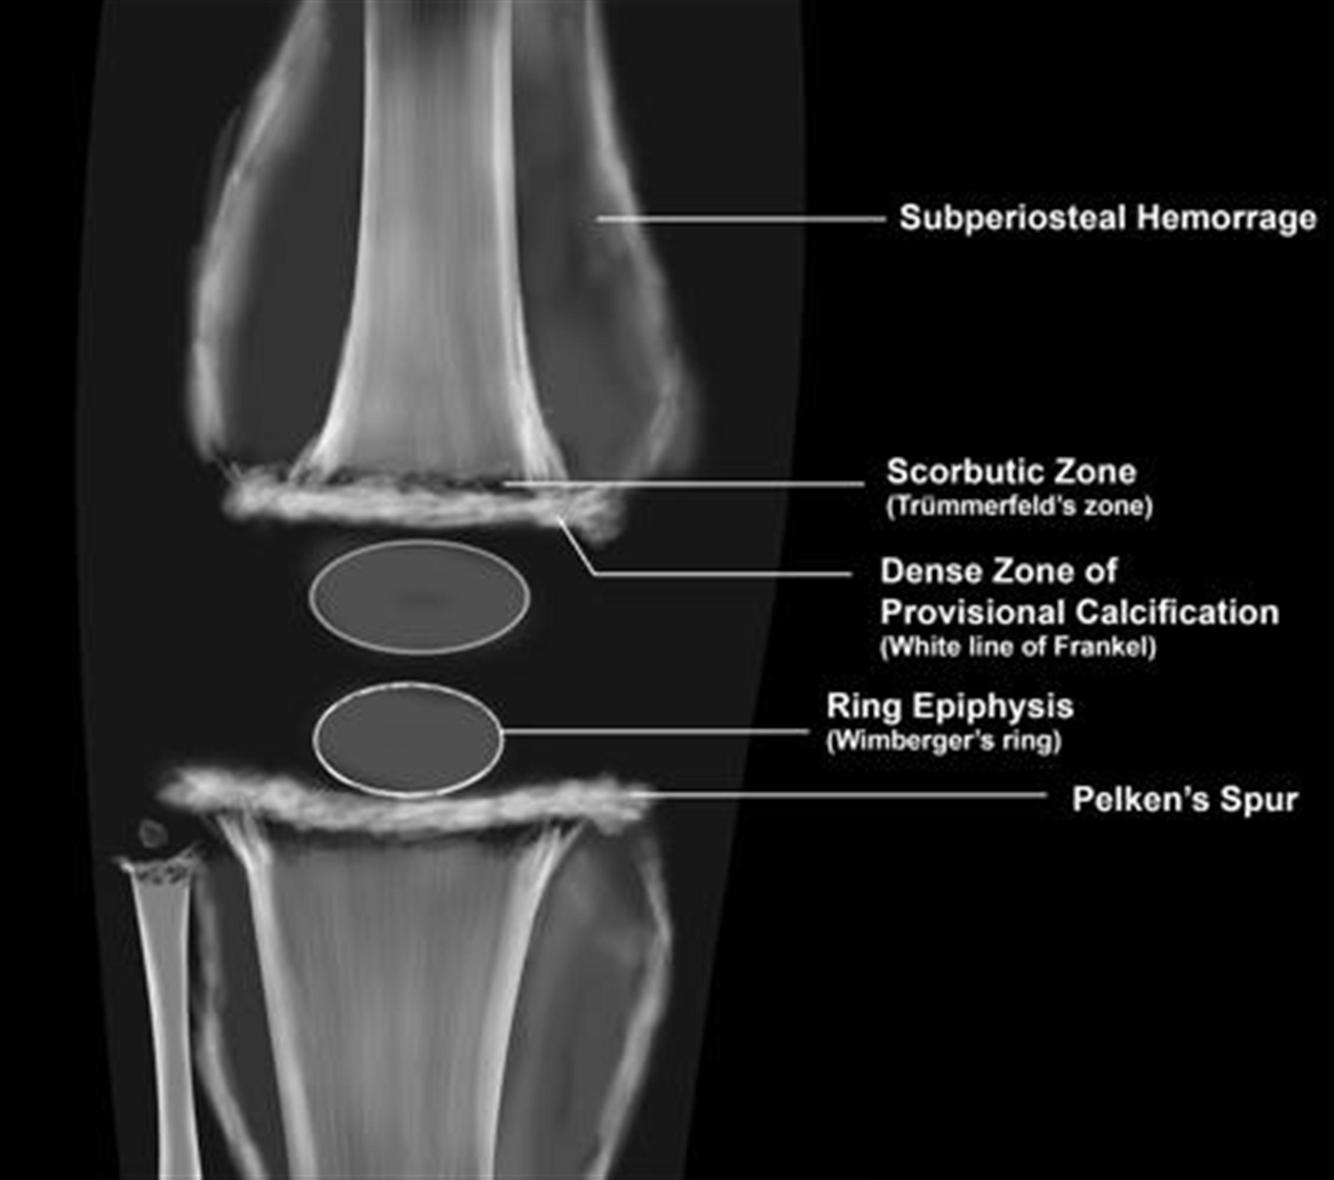

scurvy